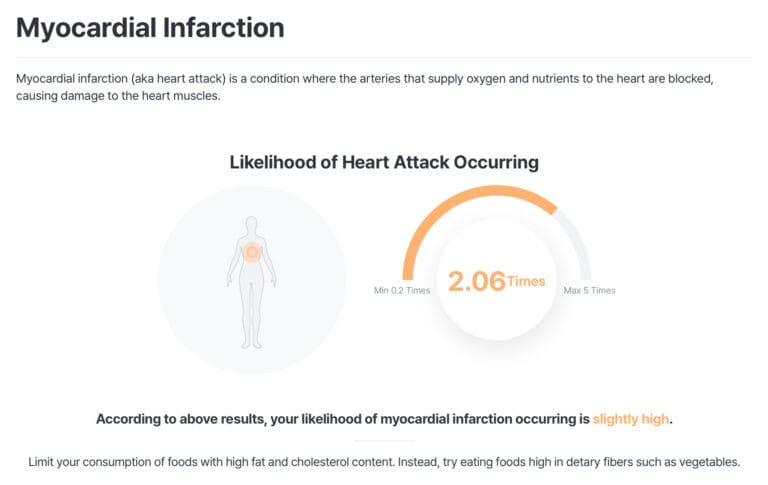

At MyDNA, we believe knowledge is power. Predictive DNA testing provides personalised insights into your genetic predisposition for heart disease and related conditions. Here’s how our DNA testing service empowers individuals: